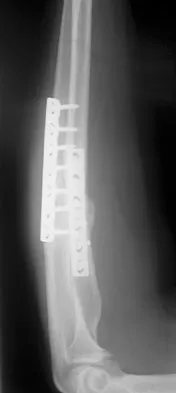

Which of the following choices best describes the fracture pattern shown in Figures 2a through 2c?

Explanation

The fracture pattern shown in the radiographs is a fracture of the posterior column. The only line interrupted on the AP pelvis is the ilioischial line. The obturator oblique view shows that the iliopectineal line is intact as is the outline of the posterior wall. The iliac oblique view shows an interruption of the ilioischial line and an intact anterior wall. Therefore, this fracture is a fracture of the posterior column. Letournel E, Judet R: Fractures of the Acetabulum, ed 2. Berlin, Germany, Springer Verlag, 1993.